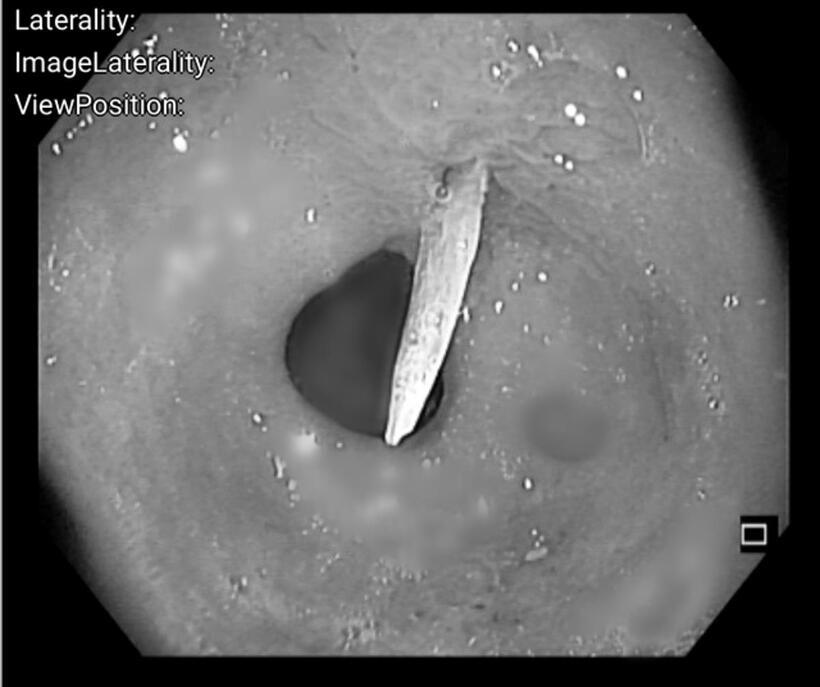

Hình ảnh dị vật dài khoảng 4cm, nghi là xương cá, đâm xuyên qua thành sau dạ dày vào trong ổ bụng. Ảnh: Sức Khỏe & Đời Sống

Trước nguy cơ gặp biến chứng nguy hiểm như viêm phúc mạc, nhiễm trùng ổ bụng hay xuất huyết tiêu hóa, các y bác sĩ khẩn trương tiến hành nội soi can thiệp. Hình ảnh nội soi cho thấy dị vật sắc nhọn cắm sâu vào hang vị dạ dày, gây ra tình trạng phù nề và chảy dịch mủ tại chỗ.

Các bác sĩ sử dụng kìm chuyên dụng để gắp gọn dị vật ra ngoài, kẹp Hemoclip được sử dụng để cầm máu, đóng kín lỗ thủng, giúp bệnh nhân tránh được cuộc mổ mở nguy hiểm.